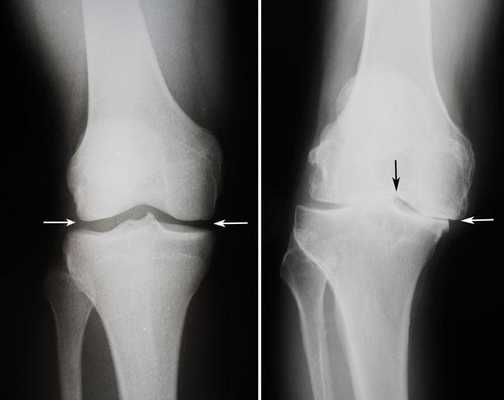

Артроз коленного сустава на рентгене.

Посмотрите на рентген, на нем вы видите, до какой степени при запущенном гонартрозе изношен гиалиновый хрящ, обеспечивающий гладкое скольжение суставных поверхностей. Концевые участки костей грубо деформируются нарушая функции сгибания и разгибания конечности вызывая интенсивный болевой синдром.

Динамика болезни на рентгене.

Откладывать хирургию при гонартрозах 3-4 степени чревато деформацией позвоночника. Это происходит из-за хромоты. Дегенеративные процессы артроза глубоко затронут кости, из-за чего они приобретут хрупкость, потеряют плотность и зафиксировать к ним компоненты импланта станет сложно.